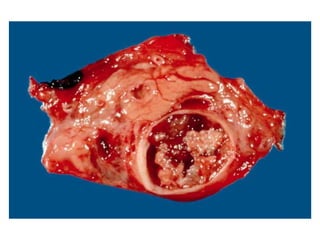

Definition: Is a collection of amylase rich fluid enclosed in a wall of fibrous or granulation

tissue.

Aetiology: after an attack of acute pancreatitis**, in chronic pancreatitis, and post

pancreatic trauma

Pathogenesis: Formation >/= 4 weeks from the onset of acute pancreatitis. Thick fibrous

capsule – no true epithelial lining. Due to ductal distruption, strictures, calculi, tumours.

Composition: Similar electrolyte concentrations to plasma

High concentration of amylase, lipase, and trypsin.

Occurrence: Most common cystic lesions of pancreas, accounting for 75-80% of such

masses

Single *, maybe multiple, or loculated

Location: Lesser peritoneal sac in proximity to the pancreas

Large pseudocysts can extend into the paracolic gutters, pelvis, mediastinum, neck or

scrotum